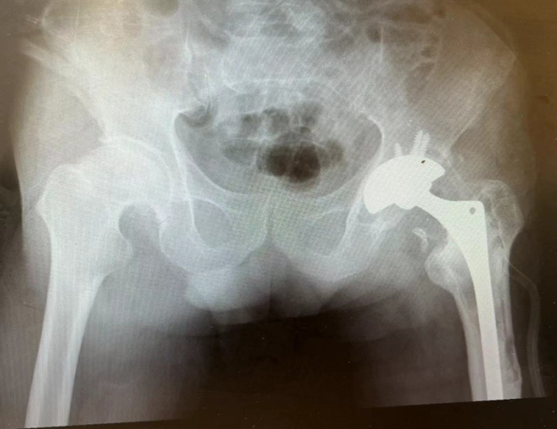

年长日久,假体逐渐出现磨损松动,近3年,跛行疼痛逐渐加重,特别是入院前1个月,已经疼痛到无法行走,自行服用止痛药物也无法缓解,前段时间,便来到石门县中医医院骨伤二科就诊,影像检查提示左侧髋关节股骨柄假体松动。

( 术前X光片 )

入院后进一步检查评估,股骨柄周围发生骨质溶解,骨皮质变薄,假体远端向外侧倾斜,髓腔扩大,骨皮质接近戳穿,髋臼合金假体稳定,聚乙烯内衬及合金股骨头假体有磨损。